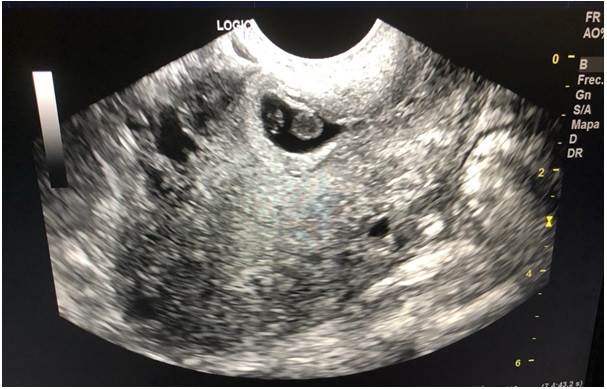

A tenor de esa última indicación, acude a servicio de consulta externa con un resultado reciente de laboratorio que muestra β-HCG de 6300. El médico tratante realiza ecografía que reporta ovillo vascular de 2.2 x 3cm en área de cicatriz de histerorrafia (Figura 2), se decide su ingreso para resolución quirúrgica (legrado instrumental).